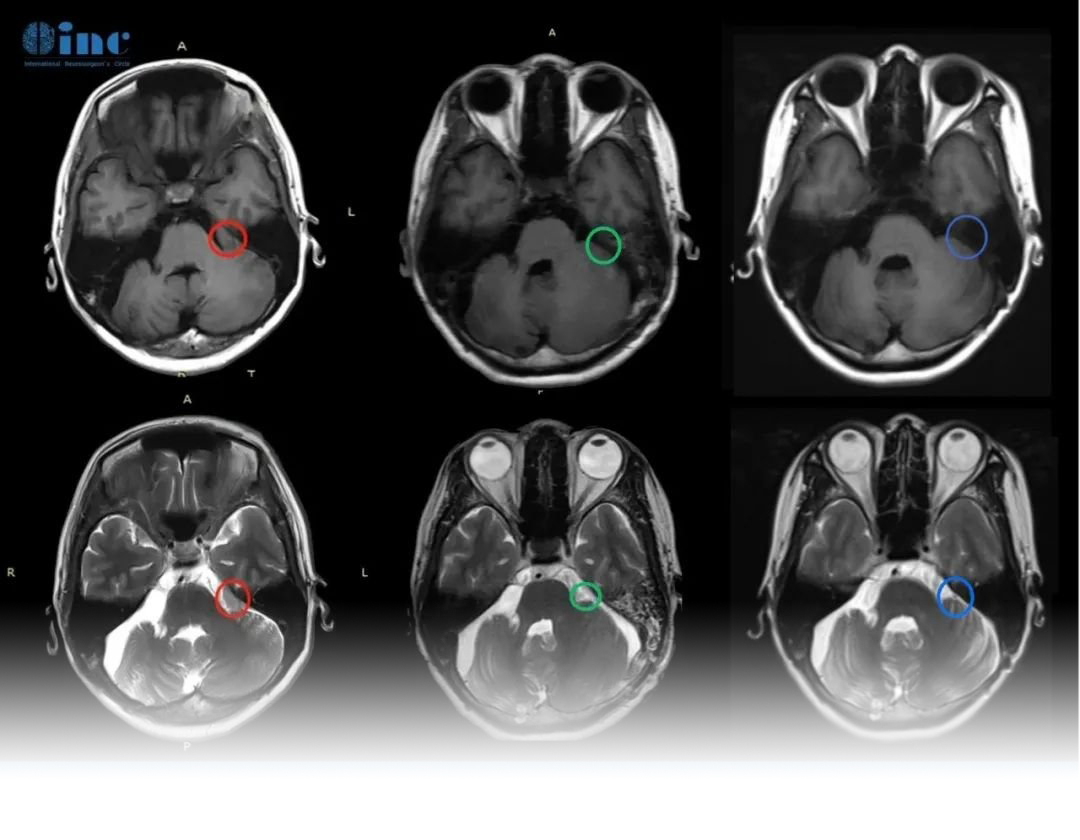

“近期的MRI好,没有肿瘤复发或任何不良副作用。所以情况很好,都在按计划进行。建议2年内做一次新的核磁复查。”巴教授在术后2年的随访中回复道。

术后1个月INC巴教授对孟女士视频随访时,恢复良好,无面瘫,原有听力正常,能与教授正常沟通。教授看过孟女士的术后影像,表示她脑内的脑膜瘤已经得到顺利全切,面神经功能和听力得到保留,她可以像正常人一样生活。